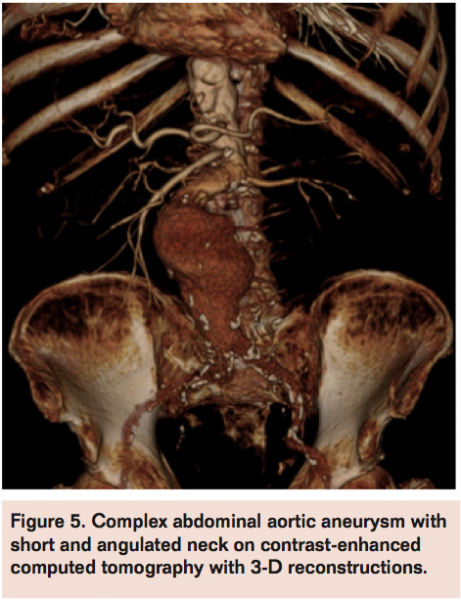

The decrease in open surgery volume for AAA repair in the last decades after the introduction of EVAR is mainly justified by well-demonstrated, consistently lower perioperative risks with new mini-invasive techniques despite the more uncertain durability often requiring reinterventions.9,10 Development of more advanced technologies and devices (fenestrated, branched stent-graft, etc.) progressively expanded the range of suitability for endovascular approaches also in the presence of more challenging and adverse AAA anatomies, such as large and angulated necks, small iliac arteries, and extensive aneurysms. Nevertheless, morphology is still the main and probably irreversible reason of concern for EVAR. Forced application of EVAR when not suited for AAA morphology (Figures 1-4) produces increased failure and complication rates. Schanzer et al reviewed outcomes of 10,228 EVAR performed in a 5-year period in the U.S. and found that only 42% of patients had an anatomy that met the most conservative definition of device instructions for use. The 5-year post-EVAR rate of AAA sac enlargement was exceptionally high at 41%. Notably, the rate of AAA sac enlargement was significantly higher in patients who underwent EVAR outside the instructions for use.11 Therefore, despite the feasibility in deployment, long-term efficacy of EVAR in forced AAA anatomies remains a main drawback allowing these cases to be better pursued by an open surgical approach.

Thereby, open aneurysm repairs are currently performed primarily in patients with more extensive aneurysms or who are not anatomically suitable for EVAR with the main limitation being an anatomically unfit proximal neck (short, large, thrombosed, angulated) or in patients with EVAR failure (eg, conversion after stent-graft migration, persisting endoleak with aneurysm growth, stent-graft rupture, etc.). Severe vessel calcification, iliac access obstruction, extensive iliac aneurysm extension, and previous aortic graft infection are other common findings in AAAs mainly reserved today for open surgery. These anatomical changes may also pose higher technical challenges for open surgery, such as raised frequency of suprarenal clamping or visceral revascularization and increases in operative duration, use of blood products, intensive care unit stay, hospital length stay, and overall complication rates when compared to repairs in more straightforward and infrarenal AAA, now routinely treated by EVAR.